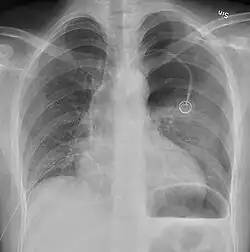

Radiografía

Una radiografía realizada en proyección postero-anterior (de atrás hacia delante) y durante la inspiración máxima constituye la forma de diagnóstico más frecuente.[38] Las imágenes realizadas en espiración, al contrario, no poseen valor diagnóstico significativo,[20] aunque pueden resultar útiles cuando existe una alta sospecha de neumotórax, pero la radiografía en inspiración aparece normal.[39] Si este es el caso, también pueden realizarse radiografías de proyección lateral, aunque esta práctica no se realiza con frecuencia.[20][31]

-

radiografía anteroposterior que muestra un neumotórax de reducido tamaño en el pulmón izquierdo, causado por una punción -

Radiografía lateral en inspiración, que muestra el neumotórax en la parte posterior -

Radiografía anteroposterior en espiración en la que también puede observarse el neumotórax

A veces puede darse una desviación del mediastino hacia el lado contrario en el que se halla el neumotórax debido a las diferencias de presión que crea esta patología. La presencia de esta desviación no implica la existencia de un neumotórax a tensión, que habitualmente se diagnostica a través de signos de gravedad como hipoxia severa y choque obstructivo.[30]

El tamaño del neumotórax (es decir, la cantidad que este ocupa en la cavidad pleural) puede determinarse midiendo la distancia entre la caja torácica y el borde del pulmón. Esto es de relevancia para el tratamiento, ya que los neumotórax de menor tamaño a menudo poseen un enfoque terapéutico distinto. Una distancia de dos centímetros significa que el neumotórax ocupa un 50 % del hemitórax.[20] Las guías de práctica clínica afirman que esta medida debe darse a partir del hilio pulmonar, con un umbral de referencia de dos centímetros para indicar la presencia de un neumotórax de menor o mayor tamaño. La medida también puede realizarse a partir del ápice pulmonar, y en este caso el umbral es de tres centímetros,[40] aunque esta forma de medición puede hacer pensar que el tamaño del neumotórax es mayor si este se encuentra concentrado en la parte superior de la caja torácica.[20][31] Aun teniendo en cuenta esto, estos métodos de medida no poseen una correlación perfecta con el tamaño del neumotórax y, aunque el TAC ofrece imágenes más precisas en este sentido, se desaconseja su uso en estas situaciones clínicas.[20]

No todos los neumotórax son uniformes; algunos ocupan solamente un pequeño espacio en un espacio particular de la cavidad pleural.[20] A veces, pueden hallarse pequeñas cantidades de líquido en la radiografía (hidroneumotórax), que puede estar constituido por sangre (hemoneumotórax).[30] En algunos casos la única manifestación de estos que se da en la radiografía es el signo del surco profundo, por el cual se da un aumento del espacio entre la caja torácica y el diafragma por la presencia de líquido.[35]